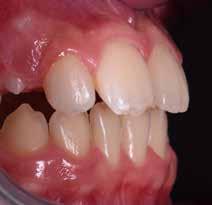

Presentazione del caso > F.V, bambino di cinque anni, presenta una malocclusione di II Classe scheletrica, III Classe dentale molare e canina destra e sinistra, morso inverso anteriore. Le arcate dentali mostrano usura degli elementi dentari anteriori a causa dell’occlusione patologica. Le linee mediane, superiore ed inferiore, sono centrate; il frenulo labiale superiore patologico per un’eccessiva estensione inter-incisale.

Il piano di trattamento prevede l’utilizzo di un dispositivo elastodontico di III Classe, da portare per due ore diurne e tutte le notti in modo passivo, senza effettuare alcun esercizio, al fine di ripristinare una relazione molare e canina bilaterale di I Classe ed il corretto avanzamento maxillare e inibire l’eccessiva crescita mandibolare. È possibile ottenere il risultato in pochissimi mesi di terapia, essendo la crescita del paziente molto attiva.

Dall’esame clinico si evince la III Classe dentale, l’inversione anteriore e l’over-jet negativo.

Una volta ottenuta la correzione del rapporto molare ed incisale, l’apparecchio elastodontico verrà portato dal paziente solo durante la notte per stabilizzare il risultato ottenuto e guidare l’eruzione degli elementi dentari per un totale di quattordici mesi di terapia. ad inizio trattamento :